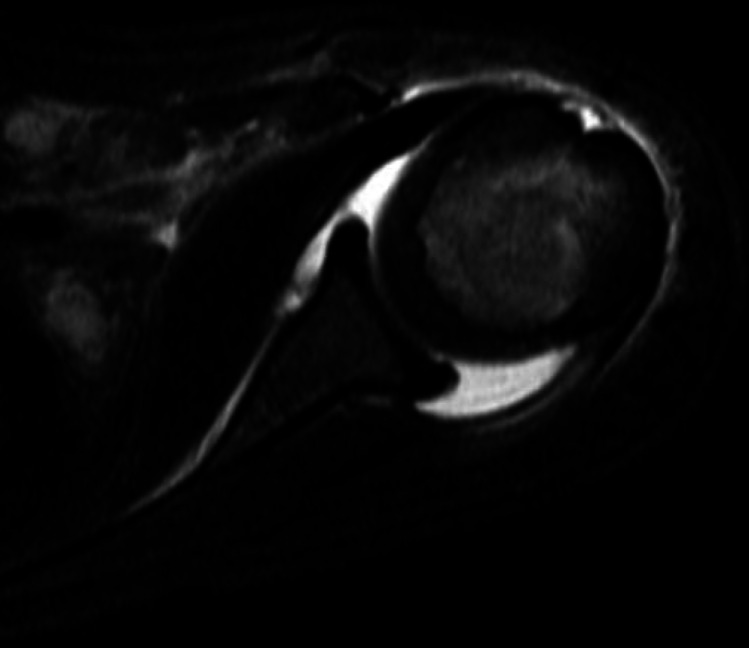

Purpose of review: For pediatric osteomyelitis and septic arthritis, 10-24% of cases occur in the upper extremity (UE). Due to delays in presentation and diagnosis, UE infections are often more complex and severe than infections of the lower extremity (LE). This review evaluates the literature from the past 6 years related to pediatric osteomyelitis and septic arthritis of the UE and provides a guide for professionals managing these conditions in children.

Recent findings: The shoulder and elbow are the most commonly affected joints, and the humerus is the most commonly affected bone. As with the LE, diagnosis of UE osteoarticular infections is based on clinical evidence, laboratory data, and diagnostic imaging. While Staphylococcus aureus is the primary bacteria identified in UE infections, there is an underappreciation of the burden from Kingella kingae as a causative organism in culture-negative patients where PCR is not performed. Septic joints should be treated with irrigation and debridement urgently, with subsequent antibiotic therapy for a minimum of 2-4 weeks. For acute osteomyelitis without abscess or concomitant septic joints, antibiotic therapy is standard of care. Methicillin-resistant Staphylococcus aureus is associated with more severe infection requiring more surgeries. Various strategies exist for managing segmental bone loss in chronic osteoarticular infections. Osteomyelitis and septic arthritis tend to occur less frequently in the UE than the LE but have a devastating impact on the health and quality of life of children around the world. Complete resolution of disease can be achieved through an individualized approach to antibiotic and operative management. Further study is needed to assess the efficacy of aspiration as a primary treatment strategy in UE joints.